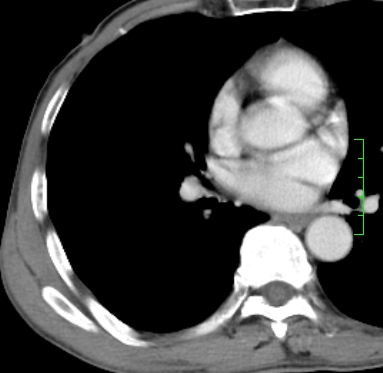

m,73y。膝关节疼痛伴双下肢水肿。入院常规胸片发现结节灶。增强为静脉期。

指套征,强化明显,近侧肺组织局限性肺气肿,考虑支气管类癌,慢支、肺气肿、双上陈旧性tb、冠脉钙化。

1)考虑右肺下叶周围型肺癌。2)右肺上叶及左肺感染性病变(结核可能)。3)肺气肿。4)冠状动脉钙化。